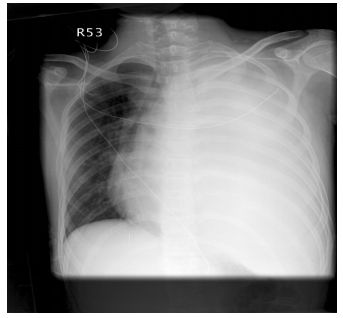

74.一個13歲的小男生來急診,主訴咳嗽和呼吸喘1星期,胸部X光如下圖所示,下列敘述何者錯誤? (A)可能是有左側大量胸水造成呼吸窘迫 (B)可能是左胸腔腫瘤造成呼吸窘迫 (C)可用胸腔超音波檢查並分辨左側胸腔的狀況 (D)可能是左支氣管塞住導致左肺全塌陷